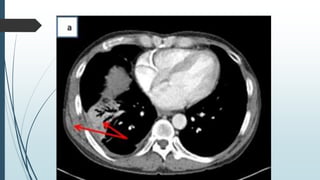

ď‚´Fluid density in pleural space & extending into

subcutaneous tissues in the chest wall or

elsewhere in abdomen

ď‚´Shows bone erosions well

Post contrast – rim enhancing fluid collections.

CT Scan Fluid densityin pleural space & extending into subcutaneous tissues in the chest wall or elsewhere in abdomen Shows bone erosions well Post contrast – rim enhancing fluid collections.